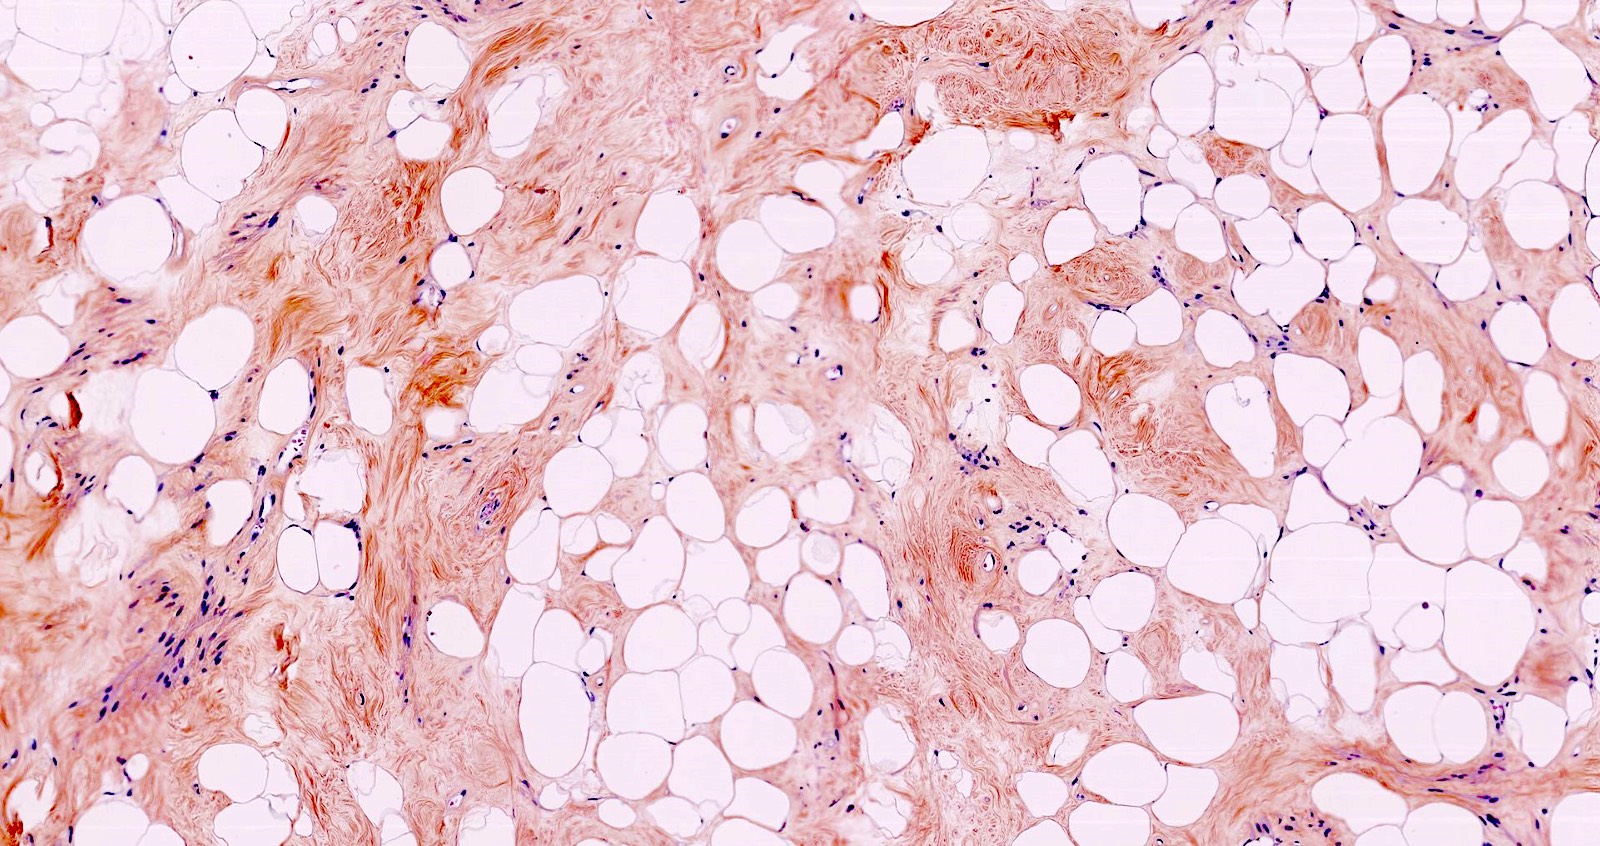

- Lipoleiomyoma:

- Tumor composed of smooth muscle cells mixed with mature adipocytes (variable quantity)